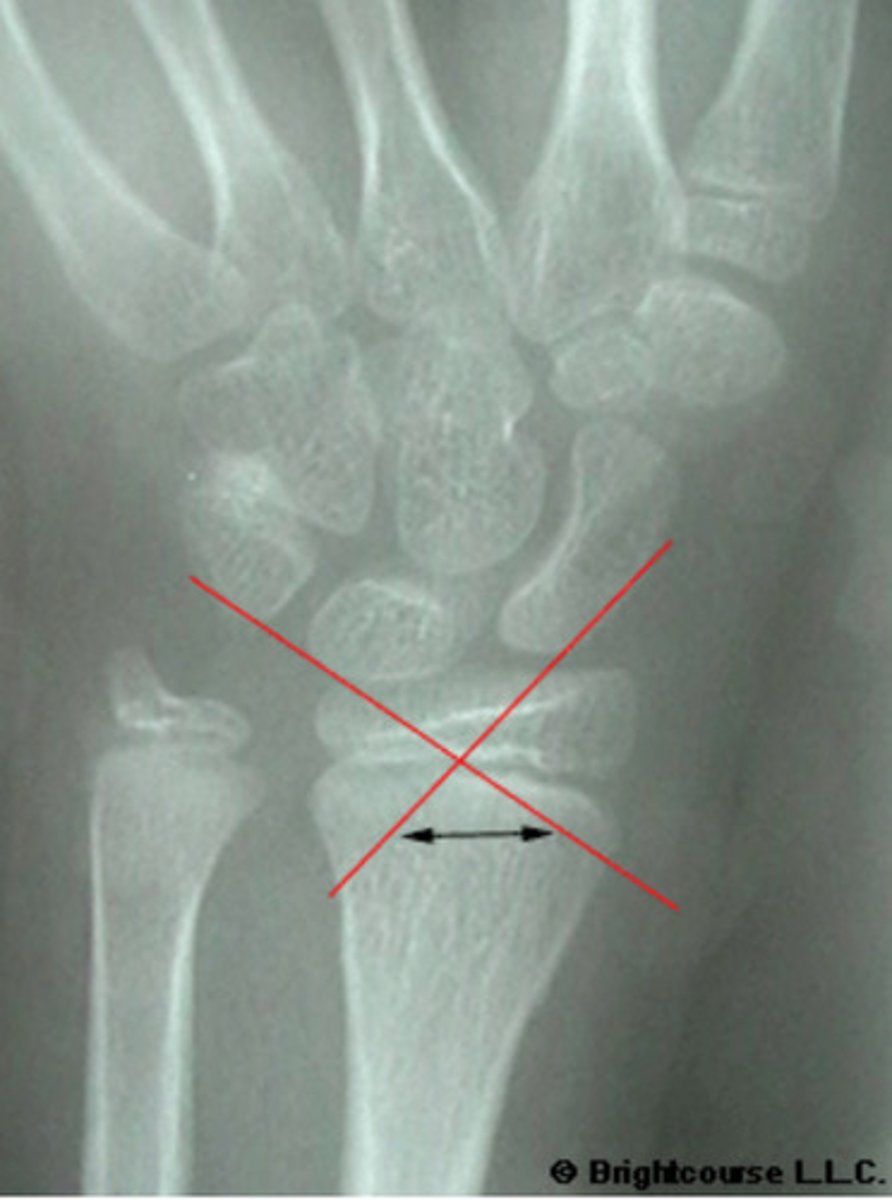

What is the normal range for the Carpal angle?

Carpal angle

What angle is being assessed in this image?

3 arcs of carpal alignment

What is being assessed in this image?

What conditions can alter the normal carpal alignment?